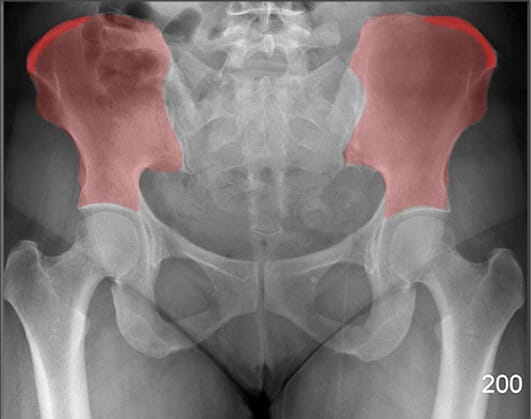

Pelvic Region

PELVIS

비구 (Acetabulum)

| 비구 (Acetabulum) |

| ✅ 대퇴골두(femoral head)가 삽입되는 골반 측면의 오목한 부분으로, AP view에서 둥근 원형 구조로 나타납니다. |

| 🔴골절, 탈구, 또는 관절 간격 이상이 있는지 확인하는 것이 중요합니다. |

폐쇄공 (Obturator Foramen)

| 폐쇄공 (Obturator Foramen) |

| ✅ 치골과 좌골 사이에 위치한 크고 타원형의 개구부로, AP view에서는 골반 하단 양측에 대칭적인 투과성 음영으로 보입니다. |

| 🔴 골반 골절에서 비대칭이나 모양 변화가 나타날 수 있는 부위입니다. |

천장관절 (Sacroiliac Joint)

| 천장관절 (Sacroiliac Joint) |

| ✅ 천골과 장골 사이의 관절로, AP view상에서 좌우 대칭적으로 좁고 긴 틈으로 관찰됩니다. |

| 🔴 간격이 좁아지거나 불규칙한 경우 염증성 질환(예: 강직성 척추염)을 의심할 수 있습니다. |

FEMUR

대퇴골두 (Head of Femur)

| 대퇴골두 (Head of Femur) |

| ✅ 비구에 삽입되어 고관절을 이루는 구형 구조물로, AP view에서 관절 중심부의 둥근 음영으로 나타납니다. |

| 🔴 대퇴골두의 위치와 관절 간격을 통해 탈구, 골괴사 등을 평가할 수 있습니다. |

대퇴골 경부 (Neck of Femur)

| 대퇴골 경부 (Neck of Femur) |

| ✅ 대퇴골두와 대퇴골 간부 사이의 연결 부위로, AP view에서 비구 아래 대각선으로 위치한 가늘고 길쭉한 구조입니다. |

| 🔴 노인의 고관절 골절이 자주 발생하는 부위로, 윤곽 변화나 불연속성을 신경 써서 관찰해야 합니다. |

대전자 (Greater Trochanter)

| 대전자 (Greater Trochanter) |

| ✅ 대퇴골의 외측 상부에 위치한 크고 돌출된 구조로, AP view에서 고관절 외측에 명확한 골 음영으로 나타납니다. |

| 🔴 고관절 주위 근육의 부착점이며 외상 시 골절 부위가 될 수 있습니다. |